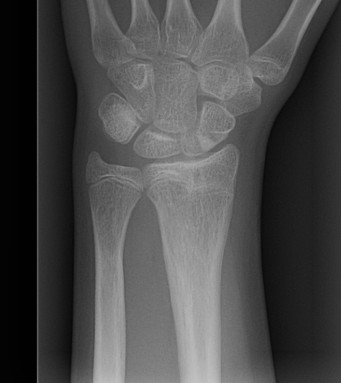

Complications

Growth arrest

SHII DR

- around 1%

- need to warn parents to represent if child develops angular deformity

Do not MUA or repeat MUA after 1 week

- only reinjure growth plate

- will remodel extremely well

- if severe, simply plan for osteotomy later if required

Physeal injuries distal ulna

- high incidence of growth arrest

Metaphyseal Radius

- incidence growth arrest also 1%